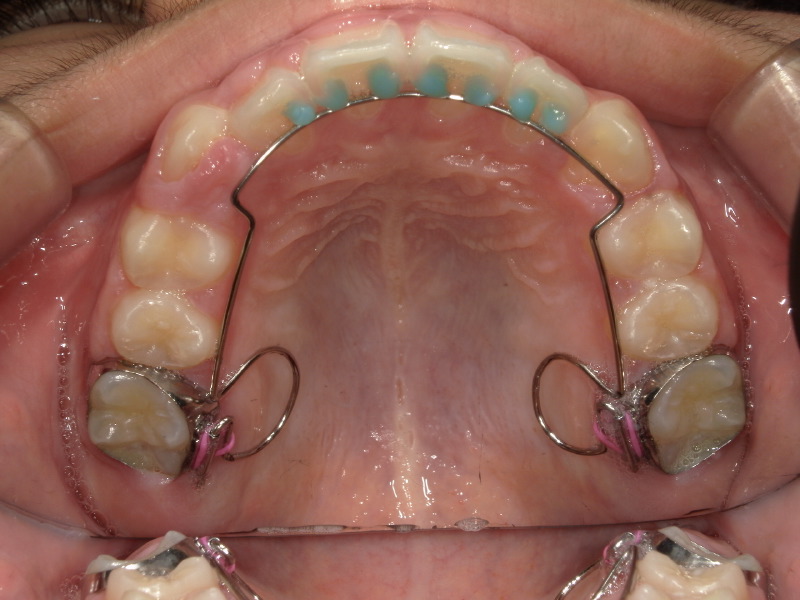

2回目の装置の経過

装置をもう少し併用したかったのでタイミングをみて再度型取りをしました。

装置をつけた日と外した後、外してから3ヶ月後の写真です。

八重歯だった歯はしっかりとアーチの中に入っていて綺麗になりました。